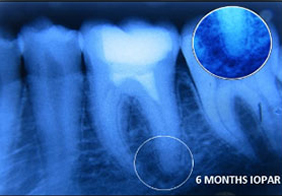

A case of combined REP in one Root and VPT in another Root.

Wound in bone (marked) in one root has healed through REP which is revealed in 6 and 12 months follow up IOPAR, the unaffected pulp in another Root Canal is protected through VPT resulting in the maintenance of validity of Tooth.

PRF Mediated REP in 21 with 26 Months Follow Up

Complete Bony Healing, Apex Closed, Lateral Dentinal Wall Thickened, PDL Apically